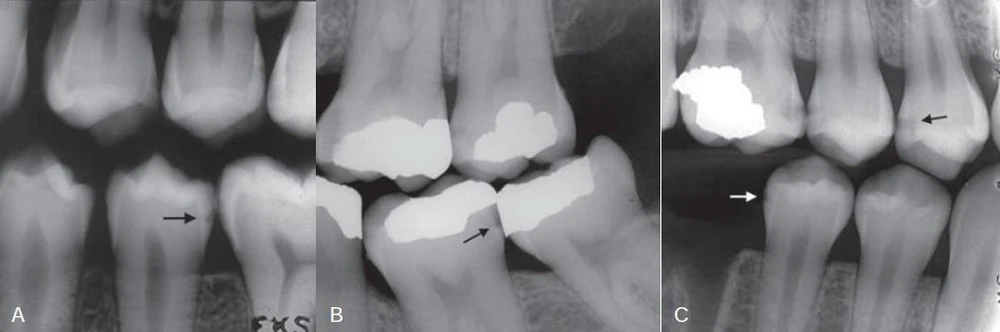

Bác sĩ đưa ra quyết định lấy bỏ mối hàn amalgam mà không gây tê (Hình 4) nhằm 2 mục đích: (1) Xác nhận tủy chết bằng thử nghiệm đáng tin tưởng nhất: thử nghiệm khoan vào lớp men ngà. (2) Lấy bỏ mối hàn amalgam cũng cho phép chúng ta đánh giá độ sâu của đường gãy để xác định nó có lan tới tủy răng hay không.

Hình 4: Gỡ mối hàn Amalgam không gây tê. Tìm thấy đường nứt ở phía xa.

Đúng như những gì nghi vấn, tủy răng đã hoại tử. Đường gãy mở rộng xuống dưới phía xa của răng chạy tới ống tủy phía xa (Hình 5 và 6).

Hình 5 (trái) Đường nứt phía xa mở rộng.

Hình 6 (phải) Đường nứt phía xa lan tới miệng ống xa gây nên hoại tử tủy.